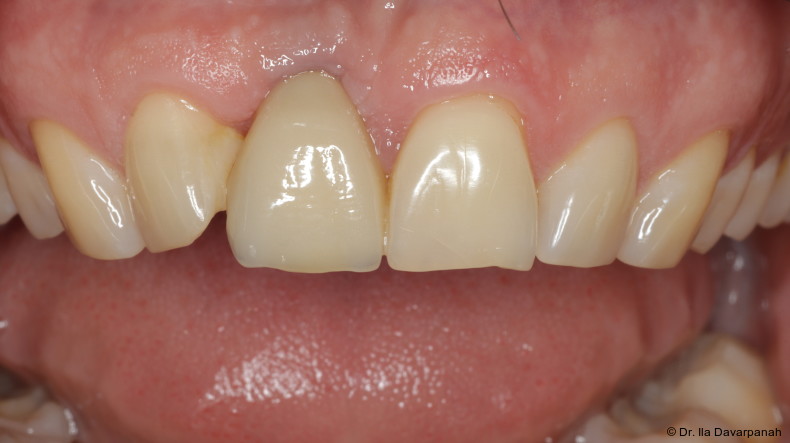

Nach Entfernung des frakturierten Implantatkörpers erfolgte eine erneute Sofortimplantation mit einem alternativen Implantatdesign. Begleitend wurden Maßnahmen zur Stabilisierung von Hart- und Weichgewebe durchgeführt.

Die postoperativen Verlaufskontrollen zeigten stabile periimplantäre Verhältnisse ohne weitere Komplikationen. Die Osseointegration sowie die Weichgewebesituation stellten sich unauffällig dar.